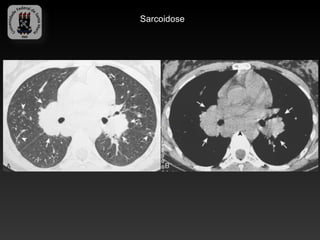

-SARCOIDOSE

-Doença idiopática caracterizada por granulomas não caseosos.

-Envolvimento pulmonar bilateral é o habitual e a linfadenopatia é a manifestação

intratorácica mais comum.

-Cerca de 10% tem radiografia de torax normal.

-Infecção sobreposta é responsável por uma significativa morbidade e mortalidade.

-Achados da TC:

-   Linfadenopatia (75-80%), calcificações em casca de ovo

-   Áreas de atenuação em vidro fosco

-   Nódulos subpleurais e perivascular

-   Espessamento irregular peribroncovascular e dos septos interlobulares

-   Predomínio nas regiões médias e superiores

-   Fibrose – complicação tardia

DPD 1- Relacionadas a doença primária -SARCOIDOSE -Doença idiopática caracterizada por granulomas não caseosos. -Envolvimento pulmonar bilateral é o habitual e a linfadenopatia é a manifestação intratorácica mais comum. -Cerca de 10% tem radiografia de torax normal. -Infecção sobreposta é responsável por uma significativa morbidade e mortalidade. -Achados da TC: - Linfadenopatia (75-80%), calcificações em casca de ovo - Áreas de atenuação em vidro fosco - Nódulos subpleurais e perivascular - Espessamento irregular peribroncovascular e dos septos interlobulares - Predomínio nas regiões médias e superiores - Fibrose – complicação tardia